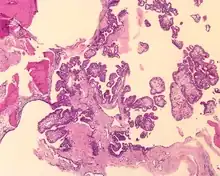

Tumors range from several millimeters up to 10 cm, with larger tumors more frequently seen in older patients. If the tumor is bilateral, it is almost always seen in a VHL patient. The tumor destroys the mastoid air spaces and extends into the middle ear and/or posterior cranial fossa.[1][3]

The microscopic appearance shows an unencapsulated, destructive growth, remodeling and invading bone. The tumor is arranged as simple, broad, non-complex papillary projections without large cystic spaces. The spaces are often fluid filled, have extravasated erythrocytes and/or inspissated material. The cells are cuboidal, usually single layered along the papillary structures, showing indistinct cell borders. The nuclei are round and hyperchromatic.[1][3][10][11]